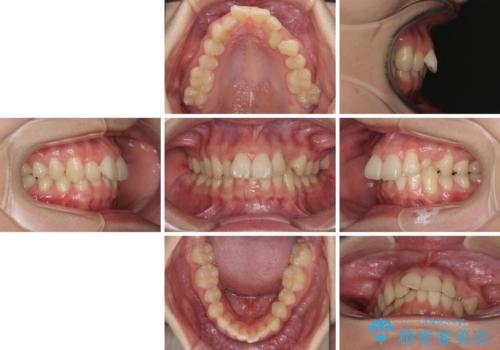

- 患者様

- 20代女性

- 咬み合わせが悪いとのことで来院された患者様です。

ぱっと見はインビザラインによる矯正治療も可能と思われましたが、歯根が最も長い犬歯がクロスバイトになっており、インビザラインでは対応困難と判断され、ワイヤー装置にて矯正治療を行うこととしました。